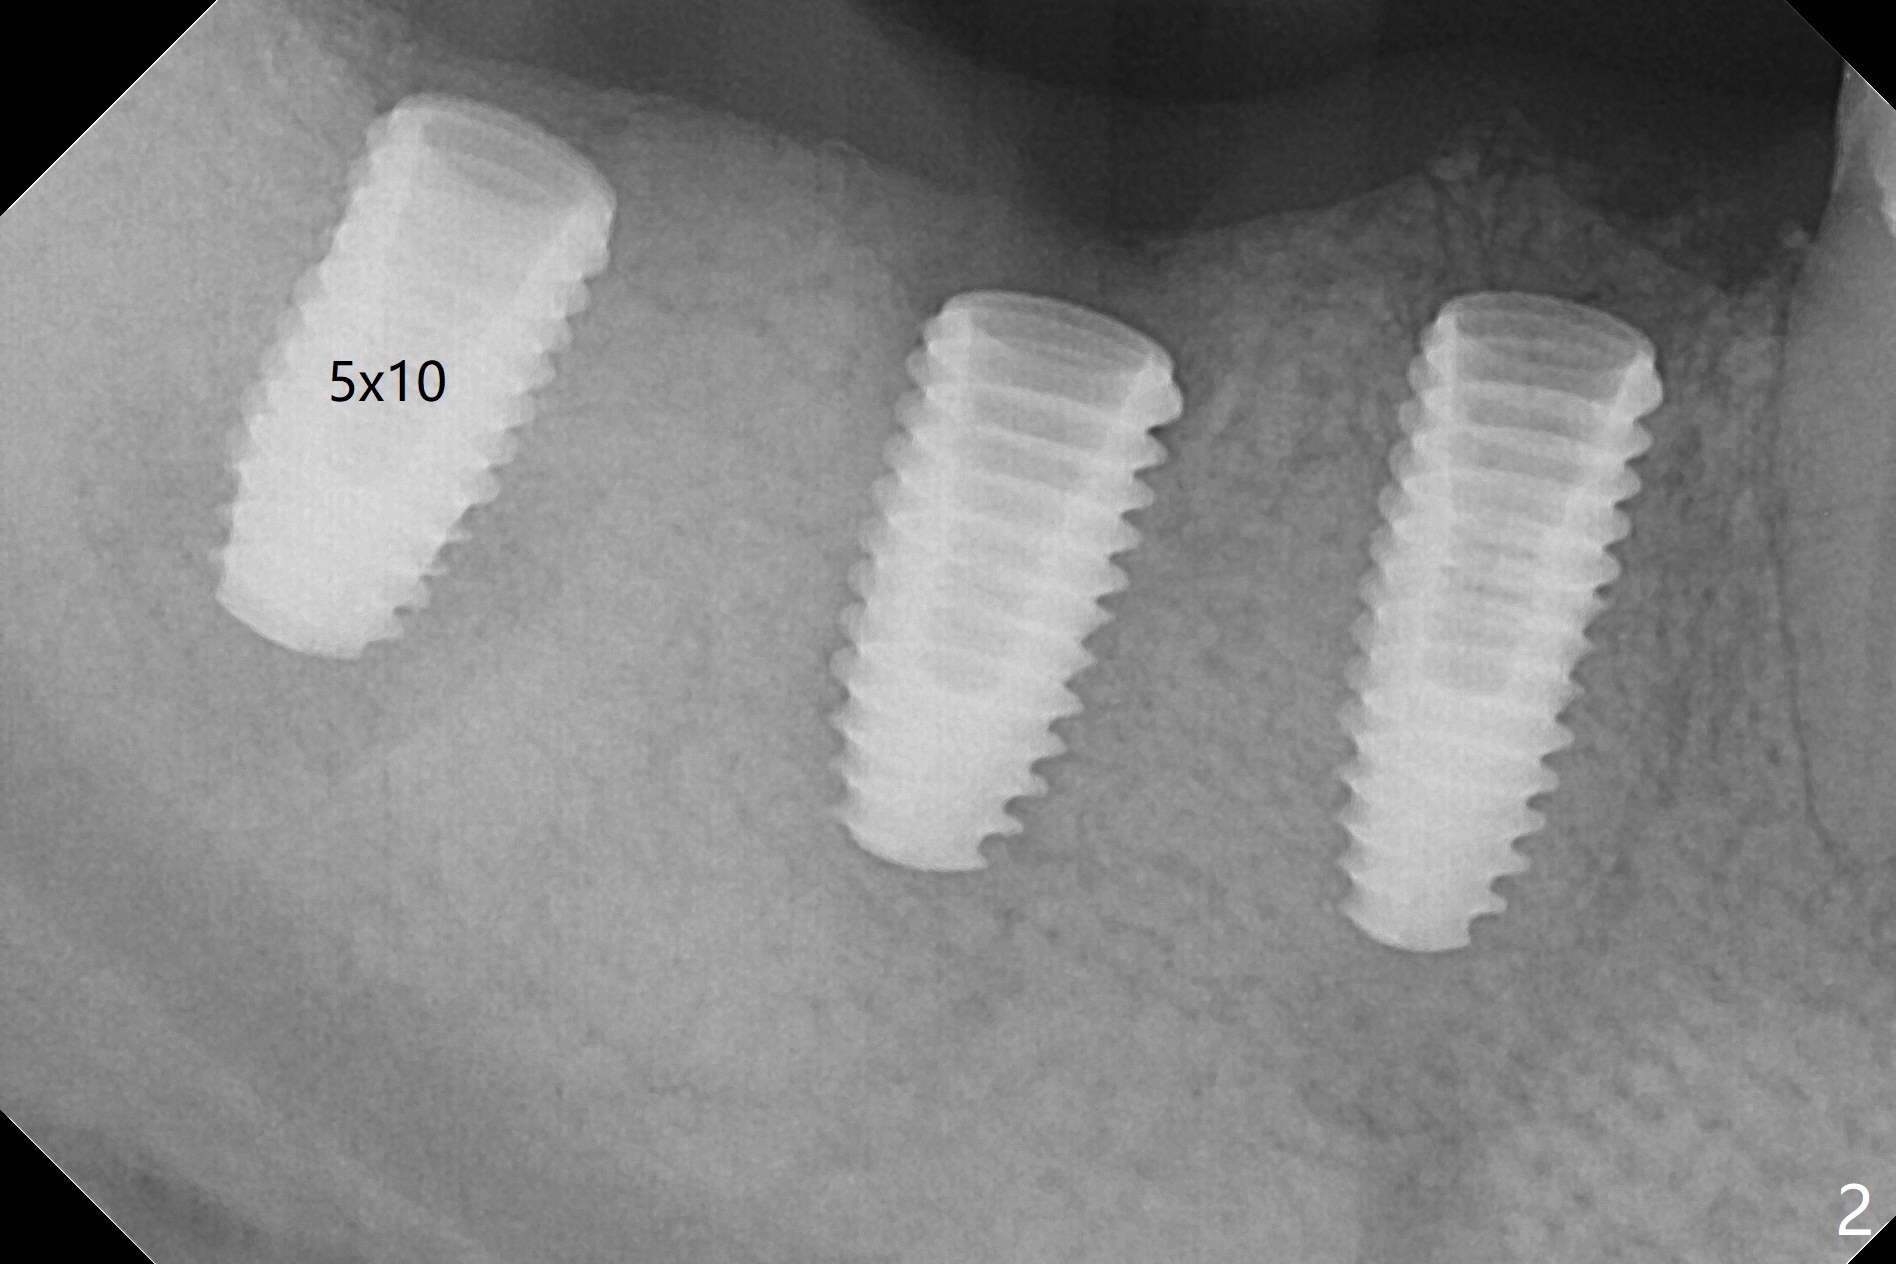

Five months post #31 implant removal with bone graft, osteotomy is initiated for a 5x10 mm implant using an existing guide. A question arises suddenly whether the bone height is reduced. Therefore a 4.5x10 mm dummy implant is placed with a fixture anchor placed at #30 (Fig.1 A). After using 4.5x8.5 mm drill with regular offset, a 5x10 mm definitive implant is placed with ~ 35 Ncm (Fig.2,3). After placement of the implant .5 mm deeper, a 8x6 mm healing abutment is placed, while the abutments return to #29 and 30 for splinted provisional (Fig.4). Two months later, the cemented abutment at #29 is loose (Fig.5) and retightened, but it remains incompletely seated for another 3 months (Fig.6). So is the one at #31 (Fig.6). After use of 4.6 and 5.6 mm bone profile drills, healing abutments are placed with apparently complete seating (Fig.7,8).